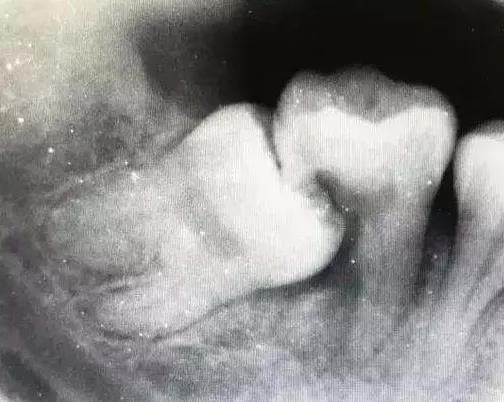

上圖的智齒已經完全長出了,亦都已經蛀到啦,噉呢個情況就要快啲去揾牙醫拔智齒啦,否則還會連累第二磨牙也一起蛀牙,唔然後仲會連累第二嚿牙都一齊蛀牙。

以上是阻生智齒

05.智齒已經齲壞

沒有良好咬合關係但是完全萌出的智齒,位置太靠裏,好難清潔到位,容易發生齜壞。智齒那麼靠裏,自己都好難意識到,這是會毀容的多數情況是痛左才發現。

06.智齒造成鄰牙病變

智齒萌發空間不足,經常會撞喺第二磨牙度,所以造成第二磨牙清潔唔易。智齒躺的時間一長,就會壓壞旁邊嘅隔離牙,然之後兩顆都同歸於盡。

呢個就係個即刻毀嘅案例。原本第一磨牙就缺嘅,智齒把第二磨牙也給頂犧牲了,種牙係唔可避免嘅